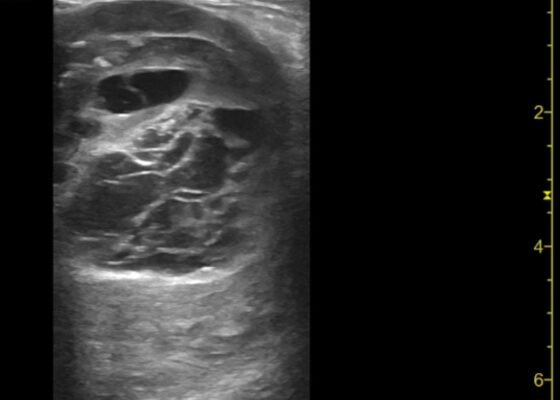

Thigh Mass Case Report

DOI: https://doi.org/10.21980/J8QD3CPoint-of-care ultrasound (POCUS) demonstrates a large, subcutaneous mass with areas of mixed echogenicity. The mass contains fluid-filled, anechoic areas with internal septations and absent doppler flow. The majority of the mass appears isoechoic to the surrounding tissues with a hyperechoic border. Computed tomography (CT) of his right thigh shows a 16 x 8.1 x 9.5 cm heterogenous, complex mass within his hamstring muscles, inferior to the femur. His lab work was significant for a white blood cell (WBC) of 17.3 (103/µL).